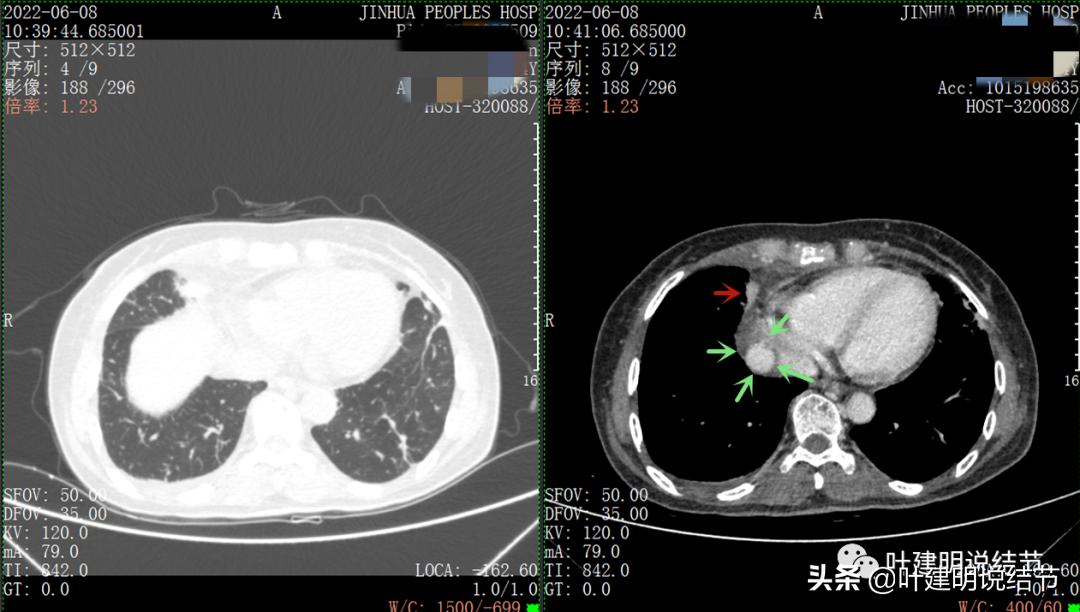

再来看看她的CT增强图像:

以下图片左侧是肺窗,右侧是纵隔窗。红色箭头示病灶,桔色箭头示无名静脉,黄色箭头示支气管,砖色箭头示上腔静脉,蓝色箭头示主动脉,紫色箭头示肺动脉。

粉色箭头示淋巴结可能

绿色箭头示近膈面处,心脏边病灶

此灶与主病灶不是完全相连的